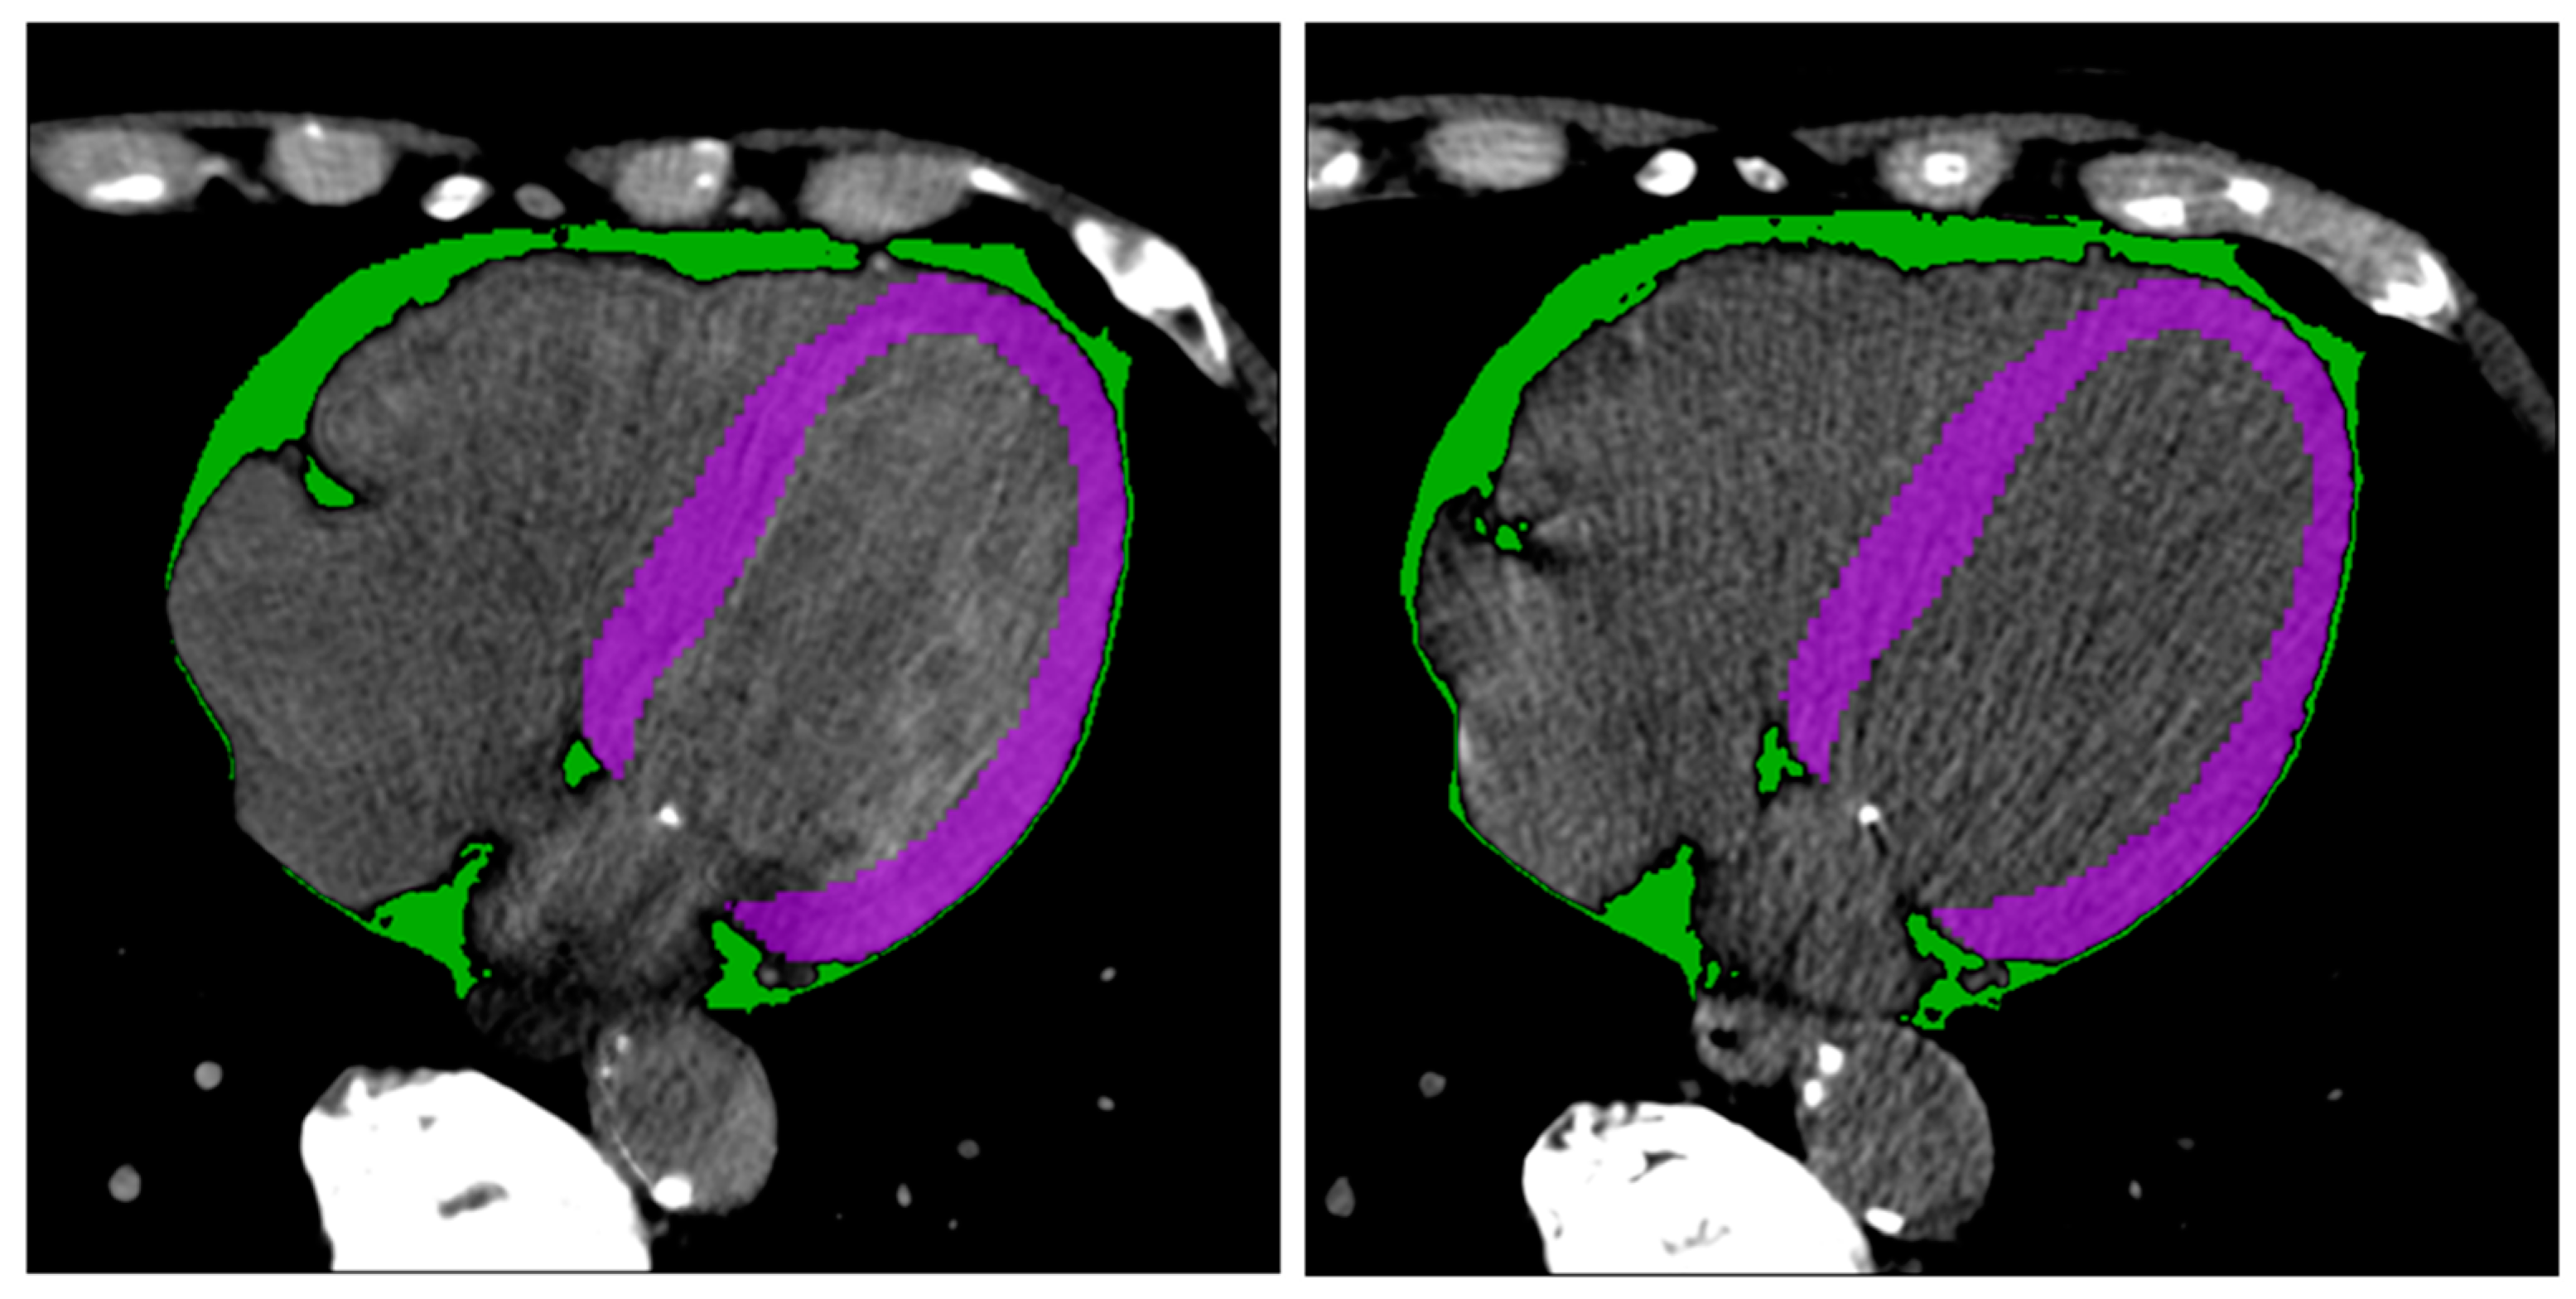

2.4. Radiomics Features Extraction